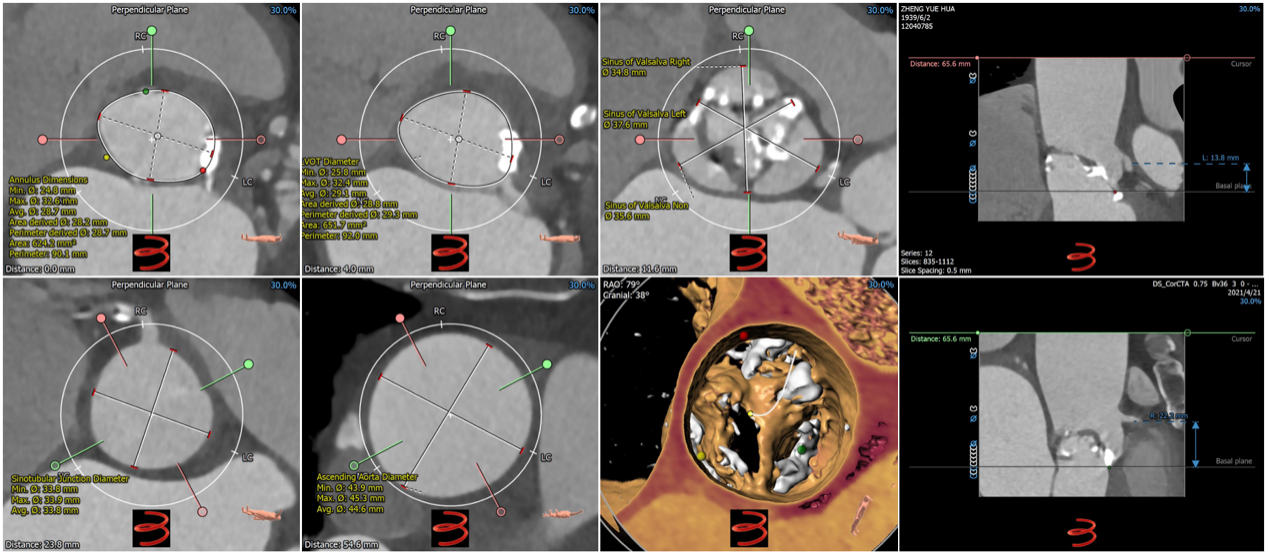

患者男,82岁,主诉:活动后胸闷加重2月,于2021年4月30日入阜外医院。患者近2个月来胸闷、气促,与活动有关,多于行走时、上楼时及情绪变化时出现,每次持续约数分钟后可缓解。体格检查:体温36.0℃,脉搏85次/min,呼吸12次/分,血压88/52 mmHg(1 mmHg=0.133 kPa)。双肺呼吸音清,未闻及干湿性啰音;心率85次/分,律齐,主动脉瓣听诊区可闻及3/6 级喷射性杂音;双下肢无水肿。入院诊断: 主动脉瓣重度狭窄、三尖瓣重度关闭不全、冠状动脉粥样硬化性心脏病、NYHA心功能Ⅲ级、高脂血症、肺动脉高压。入院心电图为窦性心律,ST-T改变。超声心动图:主动脉瓣瓣口面积为0.38 m2,瓣口峰值流速5.0 m/s,平均跨瓣压差66 mmHg,左室舒张末径48 mm,左室射血分数45%,三尖瓣大量反流,肺动脉压力57 mmHg。实验室检查:白细胞计数4.67×109 /L,血红蛋白144 g/L,血小板计数180×109 /L,血肌酐104.96 umol/L,钾离子4.55 mmol/L,NT-ProBNP 5987 pg/ml。冠脉CT评估冠脉三支未见明显狭窄。3Mensio软件评估主动脉根部解剖:功能性二叶瓣,左右融合,融合区团块状钙化;三个瓣叶钙化均匀,左冠瓣钙化延伸至左室流出道;三个瓣叶增厚,呈风湿样改变;冠脉开口高度可(L:13.8 mm,R:22.2 mm),左冠开口水平可见明显瓣叶结构,且左冠瓣叶明显增厚钙化,考虑到左右融合区存在团块状钙化,不易被植入的瓣膜扩张开,因此冠脉闭塞风险不大,注意术中球囊预扩张进一步明确冠脉闭塞风险;瓣环长短径分别为24.8*32.6 mm,周长为90.1 mm,面积为624.2 mm2;其他测量参数见图1,多平面测量参数及全主动脉评估见图2。患者高龄,拒绝外科手术,外科手术风险STS评分为2.891 %;主动脉瓣膜解剖上适合行TAVR;纠正重度主动脉瓣狭窄后的预期寿命超过1 年,符合TAVR适应证,无手术禁忌证,因此决定行TAVR。

图1患者主动脉根部CT评估

A:瓣环;B:左心室流出道;C:瓦氏窦;D:左侧冠脉开口高度;E:窦管结合部 F:升主动脉(最宽处);G:虚拟瓣叶形态及钙化分布;H:右侧冠脉开口高度。